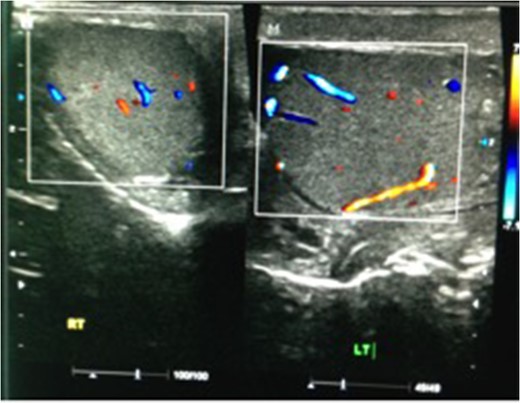

We present a case of a 37-year-old man presented to the Emergency department with a 3-day history of left testicular pain. He had no chronic illnesses and was not immunocompromised. The pain was associated with mild storage lower urinary tract symptoms. He was sexually active but had no previous sexually transmitted diseases and no urethral discharge. He had no history of trauma and had not had any similar episodes before. His examination revealed a swollen tender left testicle; equivocal for testicular torsion. A Doppler ultrasound was done which revealed increased flow to the left testicle with no evidence of testicular torsion (Fig. 1). The patient was subsequently discharged on oral ciprofloxacin, analgesia and instructed to perform scrotal elevation. The patient subsequently presented 6 h later with worsening of his pain and was reviewed and re-imaged with a color Doppler. At this time, imaging findings demonstrated reversal of diastolic flow a feature suggesting impending infarction, along with other features of acute inflammation (Fig. 2). The patient was taken to the operating room and a scrotal exploration was performed. No evidence of torsion was identified. A congested testicle was observed. No evidence of infarction or abscess formation was seen. Day 1 post-operatively the patient continued to have left sided testicular pain, now associated with lower abdominal pain. A KUB ultrasound and a repeat scrotal ultrasound were performed. These demonstrated absent flow in the left testicle (Fig. 3). On repeat exploration a dusky blue testicle was found and a left orchidectomy performed. Testicular histopathological analysis demonstrated features suggestive of acute necrotizing inflammation of the testes and epididymis as well as the spermatic cord and its vessels. Cultures of the urine subsequently showed significant growth of Escherichia coli.

Repeat ultrasound scan showing no flow within the left testicle.